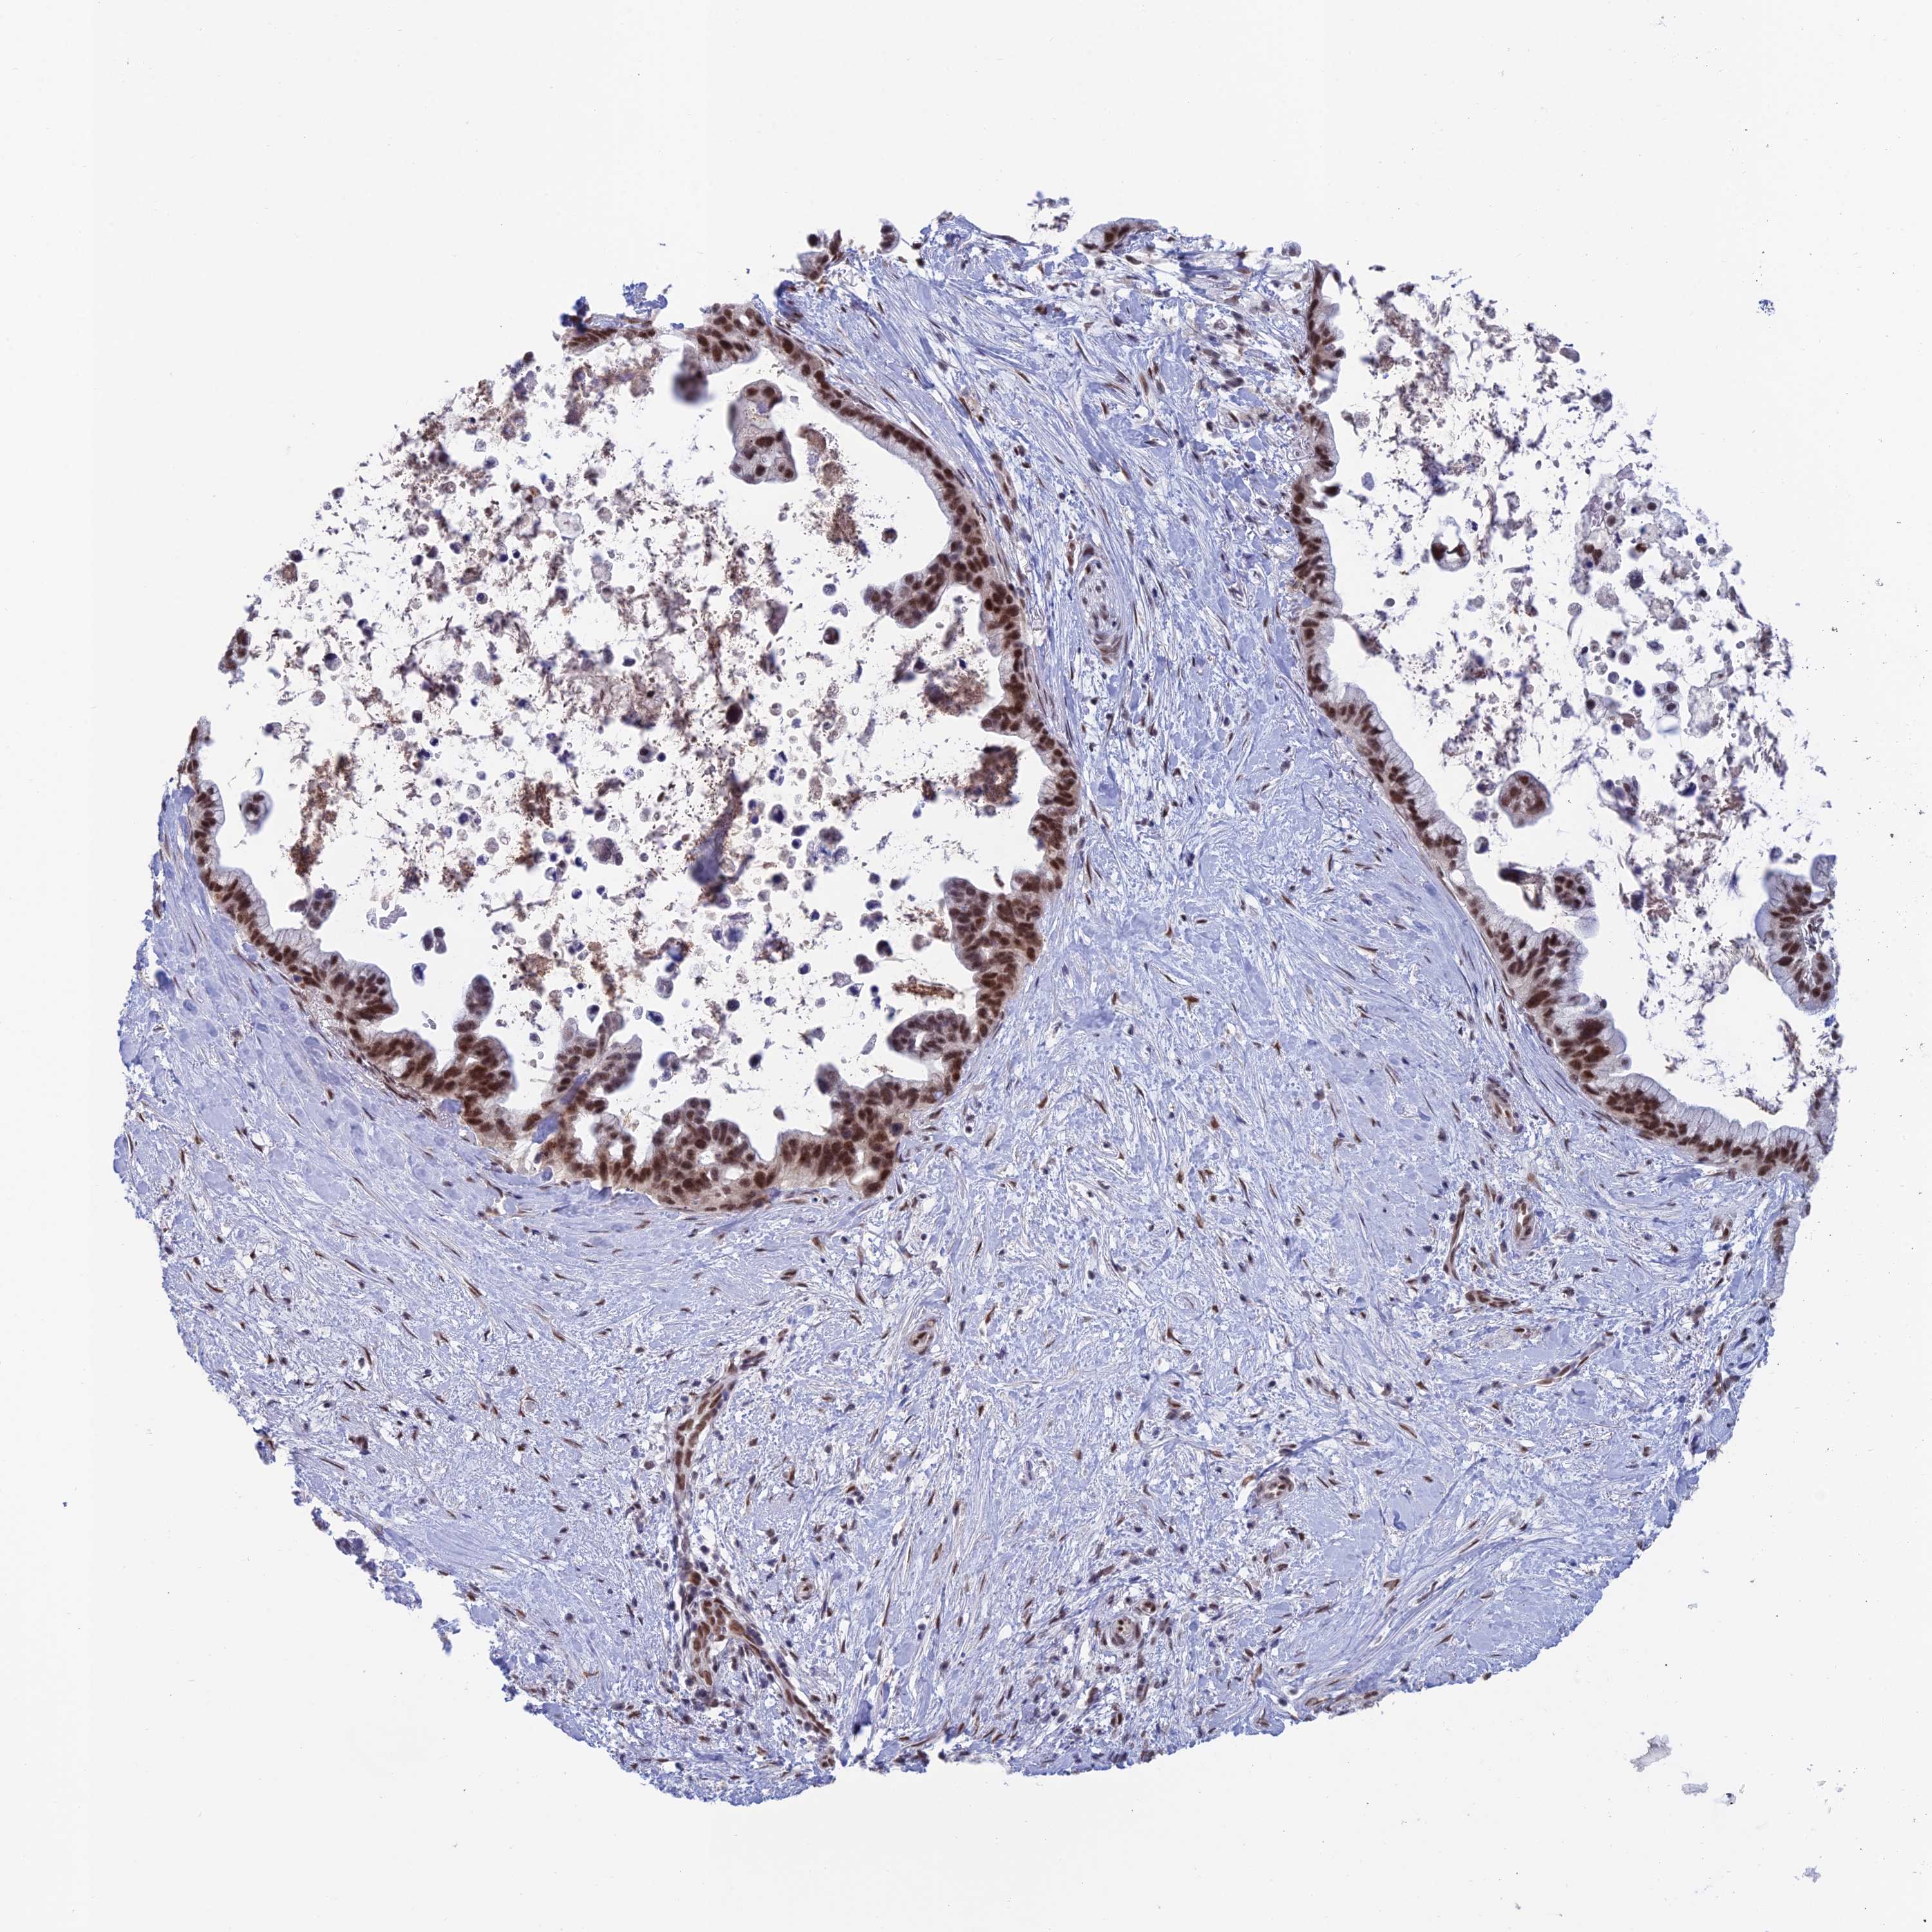

PANCREATIC CANCER - Protein expressioni

A mouse-over function shows sample information and annotation data. Click on an image to view it in a full screen mode. Samples can be filtered based on level of antibody staining by selecting one or several of the following categories: high, medium, low and not detected. The assay and annotation is described here.

Note that samples used for immunohistochemistry by the Human Protein Atlas do not correspond to samples in the TCGA dataset.

Antibody stainingi

Antibody staining in the annotated cell types in the current human tissue is reported as not detected, low, medium, or high, based on conventional immunohistochemistry profiling in selected tissues. This score is based on the combination of the staining intensity and fraction of stained cells.

Each image is clickable and will lead to virtual microscopy that enables deeper exploration of all samples and also displays staining intensity scores, fraction scores and subcellular localization as well as patient and tissue information for each sample.

Antibody HPA044615

Staining

High

Medium

Low

Not detected

Intensity

Strong

Moderate

Weak

Negative

Quantity

>75%

75%-25%

<25%

None

Location

Nuclear

Cytoplasmic/membranous

Cytoplasmic/membranous,nuclear

Adenocarcinoma, NOS